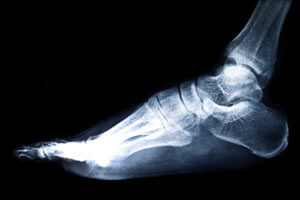

Удаление фиксатора может происходить не ранее 6 недель и не позднее 1 года. Срок его ношения определяется на основе данных рентгенологического исследования. При преждевременном удалении винта может наблюдаться расхождение костей и формирование обломков.

При внутрикостном остеосинтезе используются стержни, накостном — пластины, которые фиксируются винтами, а при чрескостном выполняется введение спиц и винтов. Во время операции используется направляющий аппарат и тонкие спицы, которые травмируют кожу только в местах их ввода. Перед хирургическим вмешательством проводится рентгенологическое обследование конечности или МРТ с целью определения степени повреждения кости и прилегающих тканей.

Чтобы определить оптимальный период для операции делают рентгеновские снимки, на которых видно размещение инородного тела относительно костей и степень сращивания перелома.